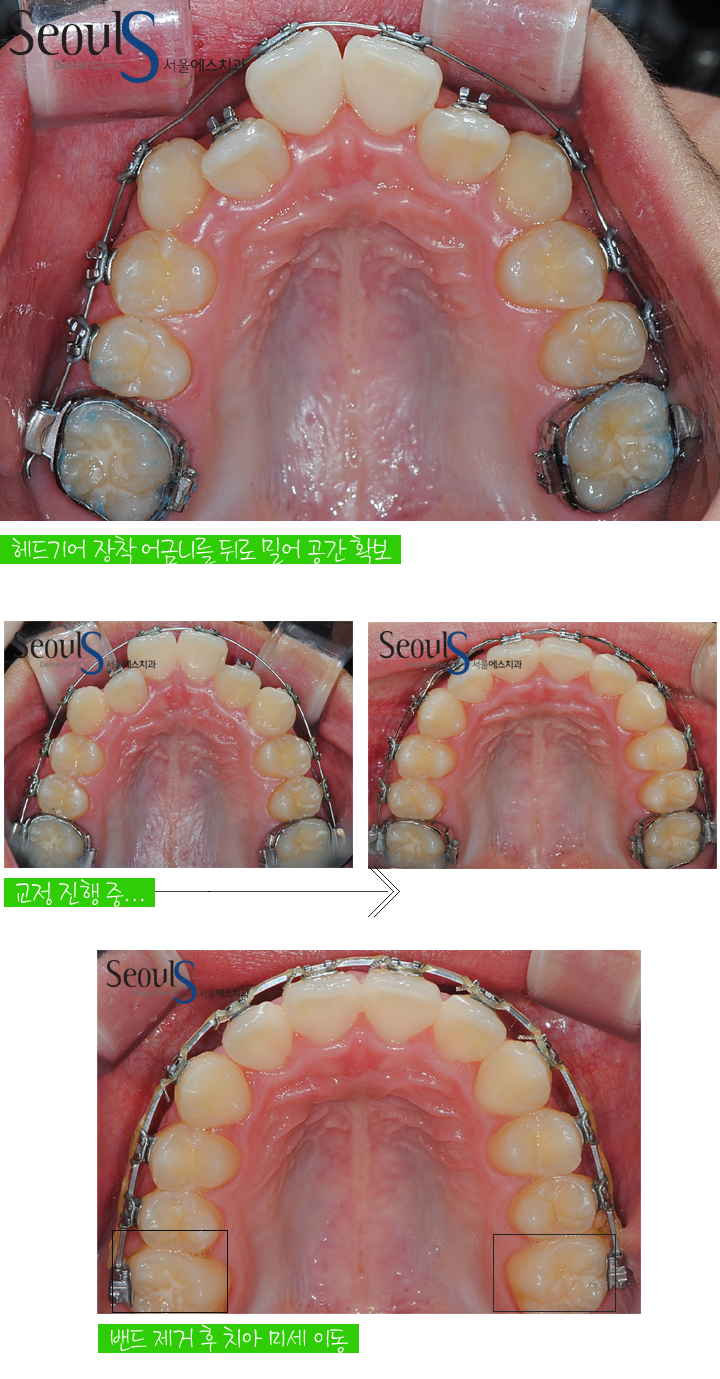

위아래 치아 모습입니다

아직 맨 끝 큰 어금니가 나오기 전이기 때문에

헤드기어 장치를 이용해서 맹출 된 큰 어금니를 뒤로 밀어 공간을 확보해

삐뚤게 난 치아를 가지런하게 이동시킬수 있었습니다

헤드기어 장치로

큰 어금니를 뒤로 밀어 공간을 확보하고

삐뚤게 난 치아를 가지런하게 이동시켰습니다

그 다음

큰 어금니에 부착되었던 밴드를 제거하고 치아를 미세하게 이동시켜 치료를 마쳤습니다

밴드는 정확한 위치에 치아를 이동시키는것이 쉽지가 않기 때문에

밴드 제거 후 정확한 위치에 치아를 이동시킬수 있는

장치를 치아의 원하는 위치에 부착시켜 치아 위치를 미세하게 조정했습니다